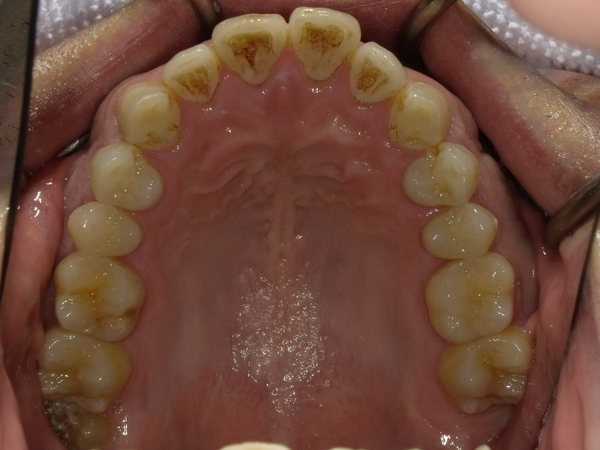

ガタガタとした歯並びや八重歯(叢生)CASE74